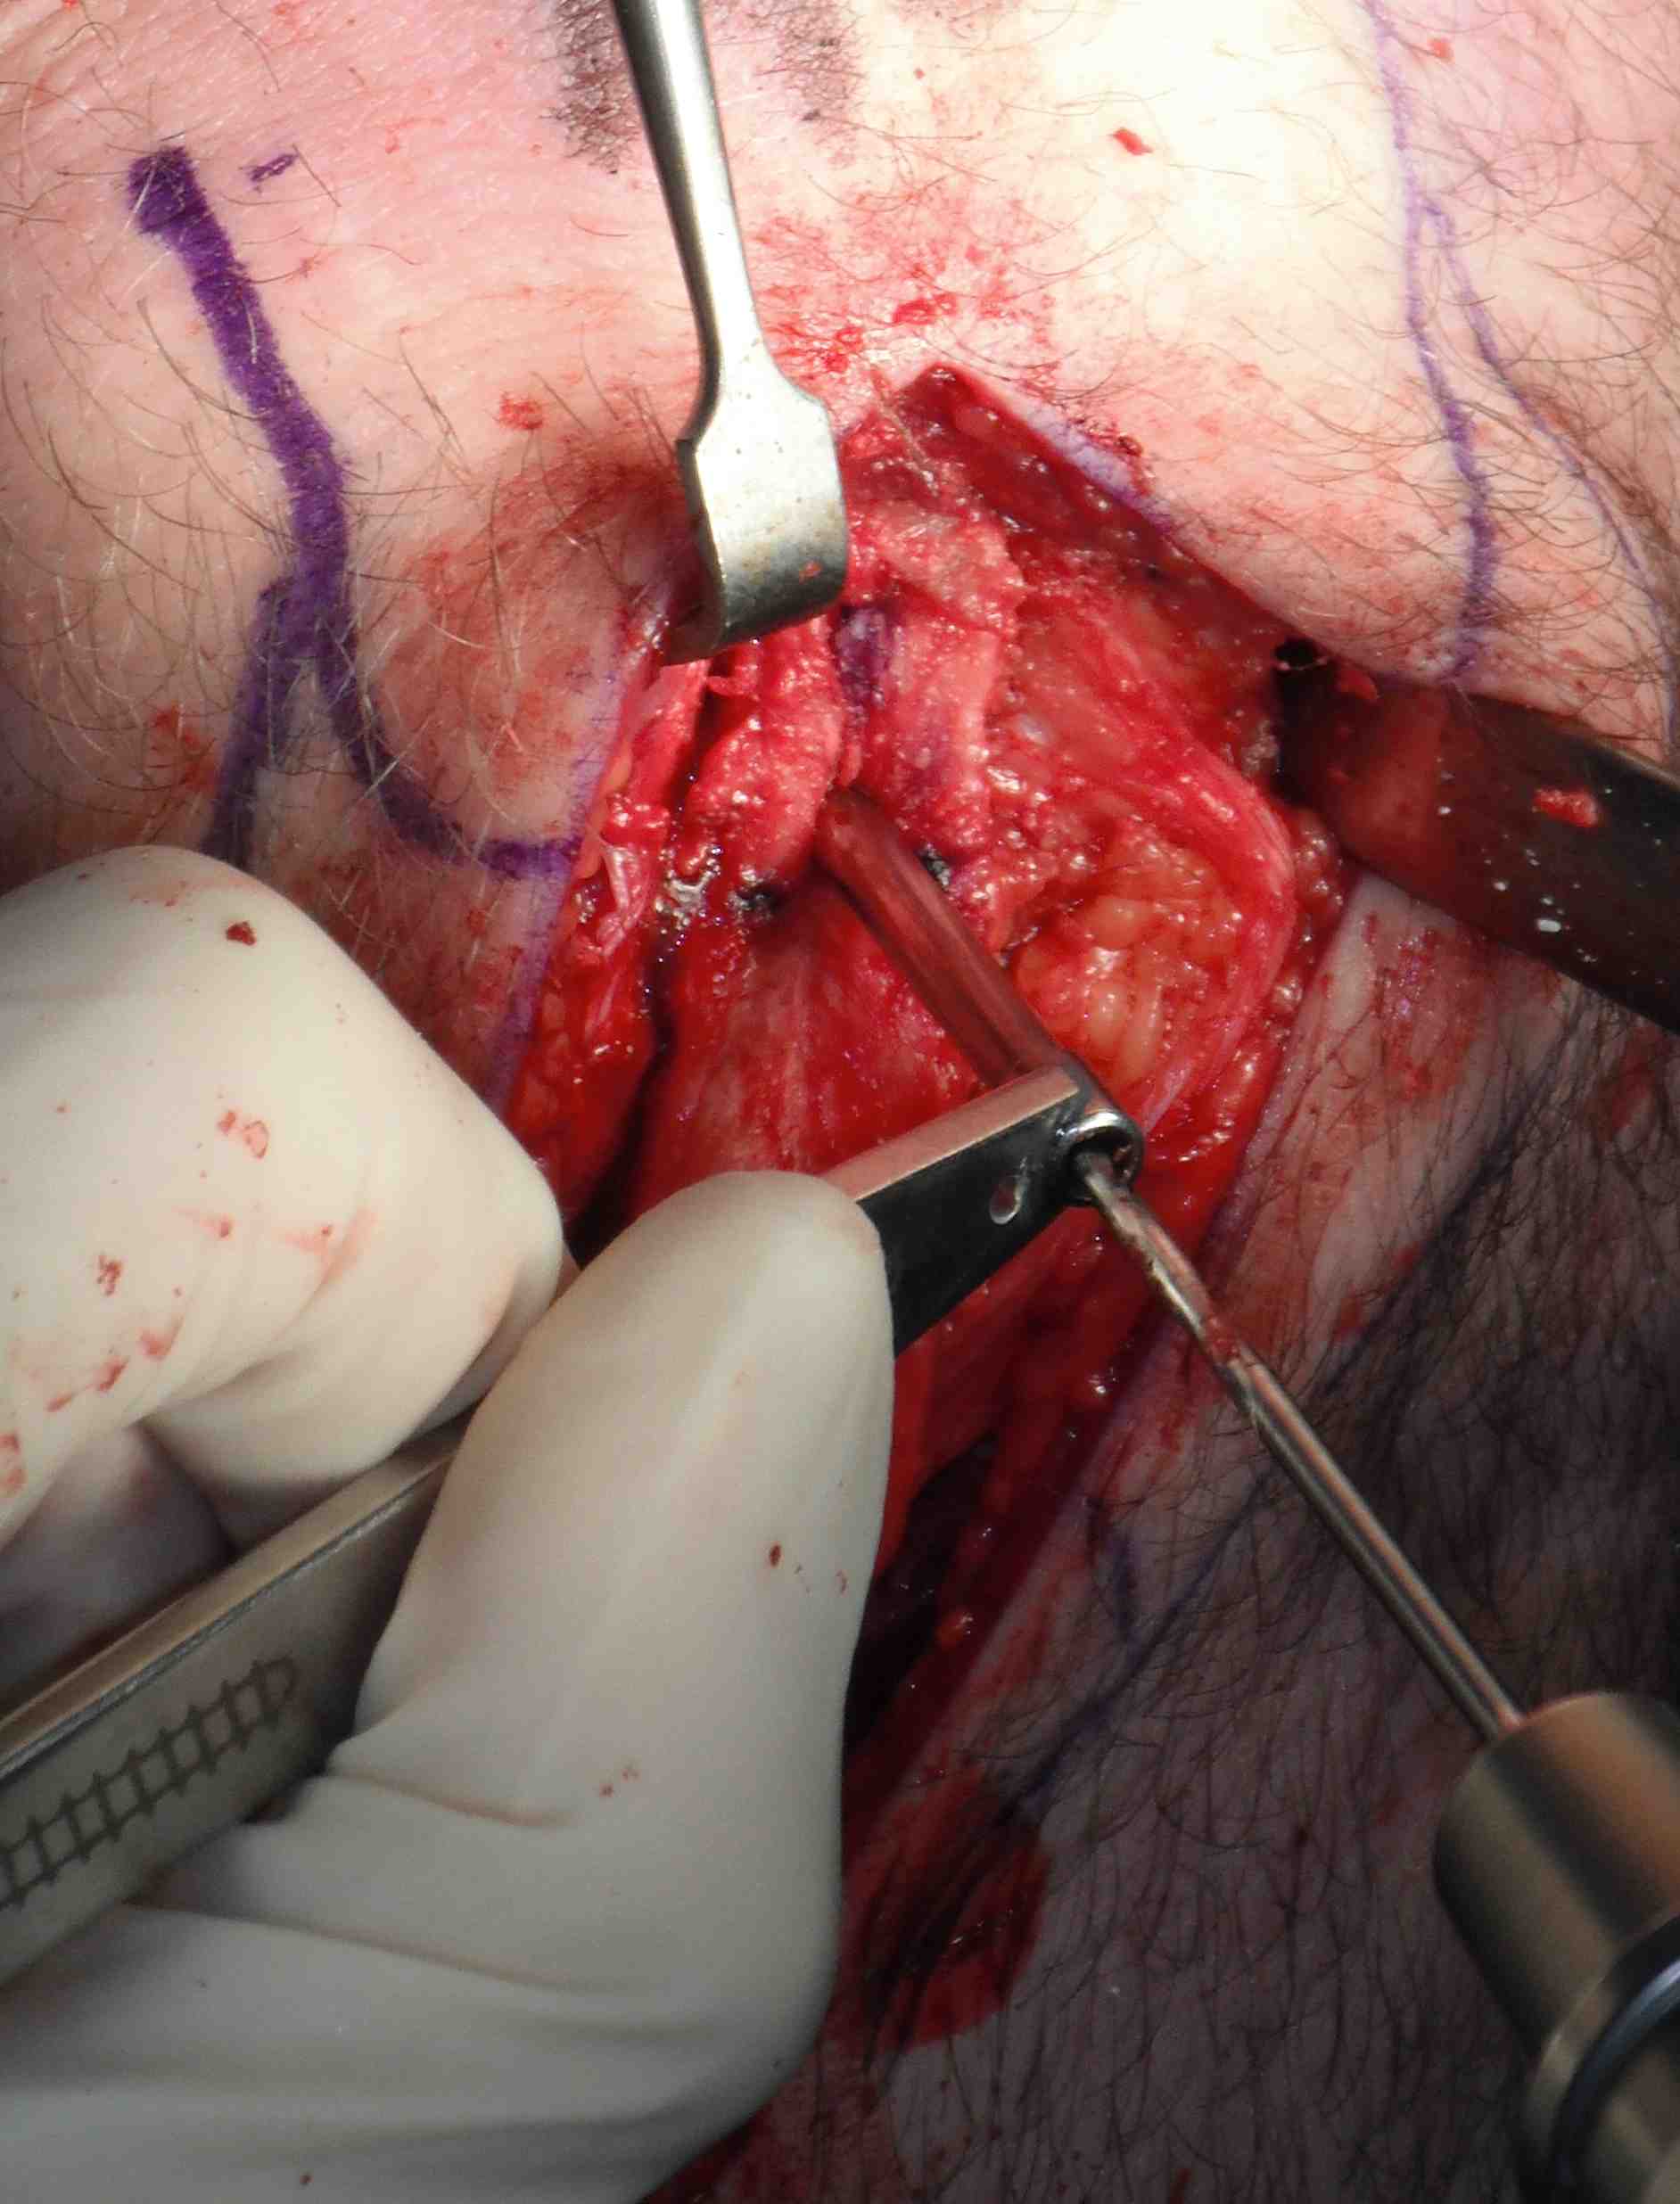

Repeat on patella side, can push patella down for exposure

- use smaller lever on patella side and be more delicate

- remove graft carefully, have to dissect off the fat pad

Graft preparation

Clean tendon of soft tissue

- decide which end will pass into femur

- usually the smaller piece

- nibble any sharp edges off especially on leading edge

- ensure whole graft will pass through 10 mm tube